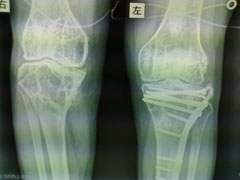

以下是引用杀毒软件在2009-7-17 11:54:00的发言:[br]骨软化症,内分泌性骨病,大骨节病均不能排除,请结合实验室检查。

以下是引用随光逐影在2009-7-17 15:12:00的发言:[br]甲状旁腺机能亢进引起多发性纤维囊性骨炎?

以下是引用zxl51642在2009-7-17 10:13:00的发言:[br]多关节骨质疏松并关节间隙狭窄,关节变形。考虑类风湿,结合病史及实验室检查(rf因子)。[br]

以下是引用dr.king在2009-7-18 20:57:00的发言:[br]甲状旁腺机能亢进引起多发性纤维囊性骨炎?进一步结合实验室检查。